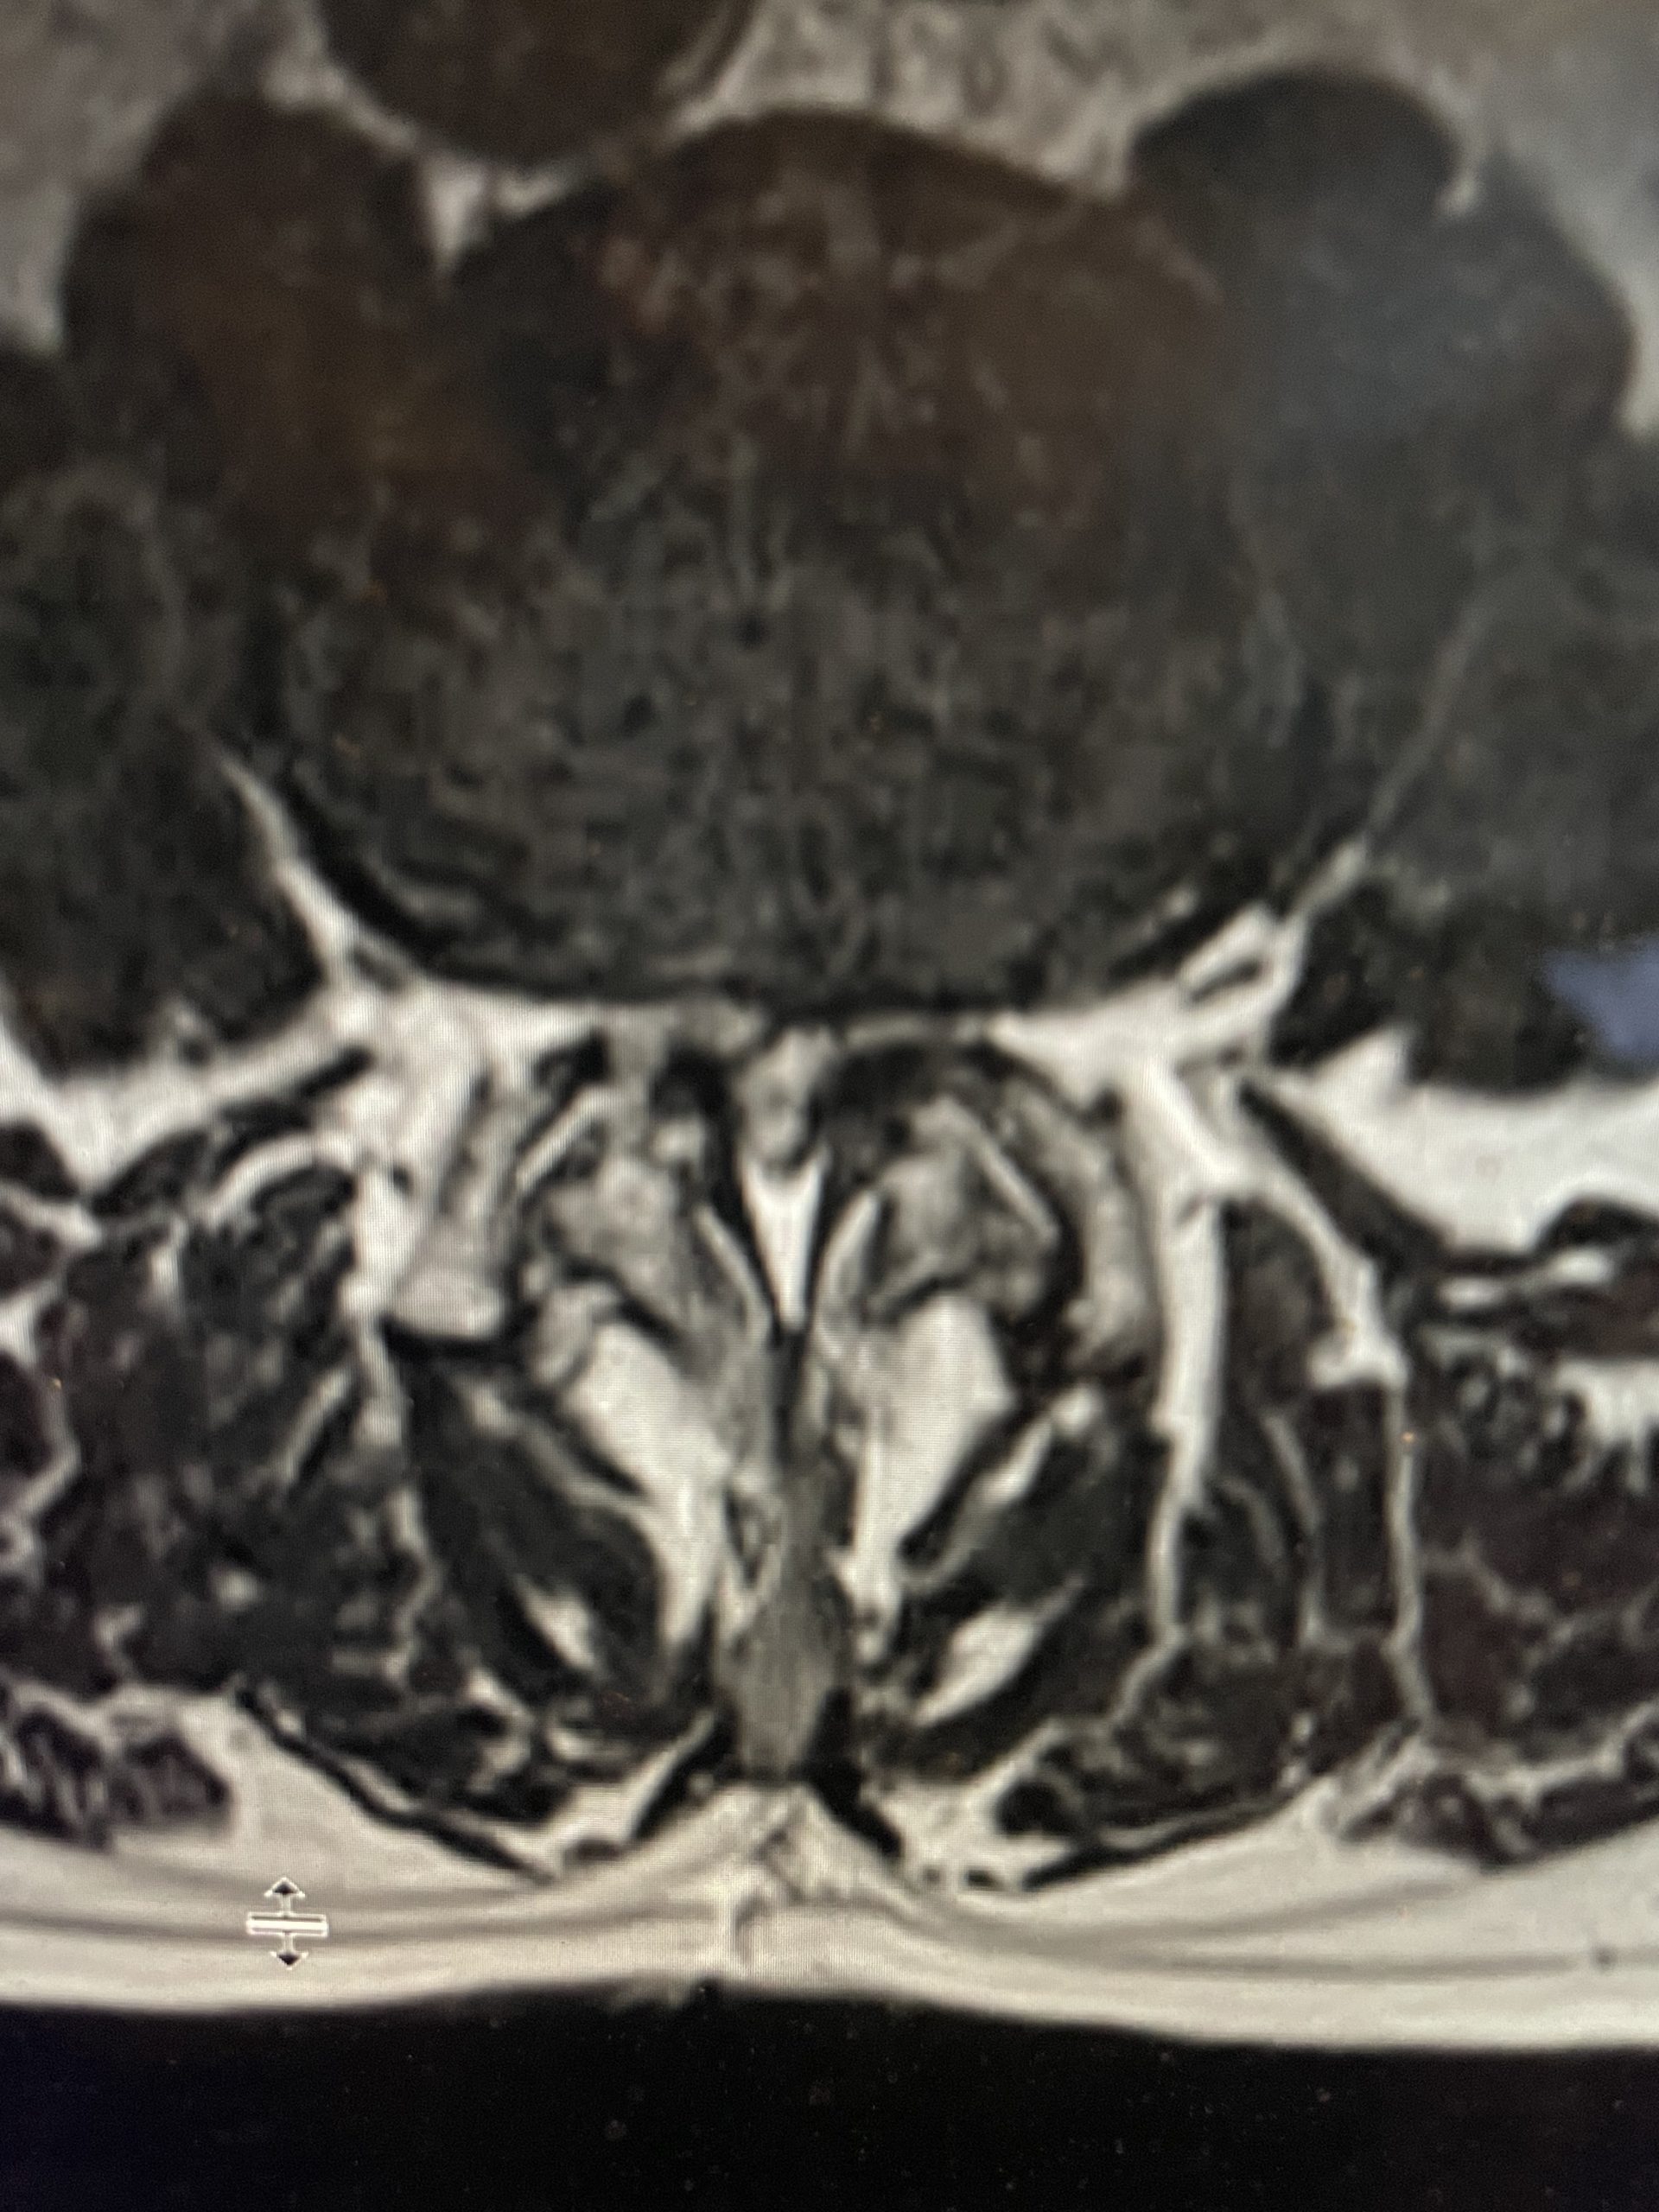

Figure 1: Sagittal x-ray after C6-7 anterior cervical discectomy showing collapse of the C5-6 disc space with fully connected anterior bridging osteophyte and C4-5 partially bridged anterior osteophyte with anterior angulation of C4 vertebral body. Sagittal T2-weighted MRI showing listhesis of C4 on C5 with C4-5 disc protrusion causing cord compression.

On the initial visit she was completely neurologically intact. We recommended physical therapy and ordered cervical x-rays and MRI (Fig 1). It appeared on her x-rays that she had a stable C6-7 fusion segment, but she also had a very collapsed C5-6-disc space. In front of that C5-6 disc space there is an obvious anterior osteophyte bridging the space, in essence autofusing that segment. Right above that at the C4-5 space there was an anterior bridging osteophyte as well with some C4 anterior angulation and listhesis with respect to C5, although the bridging bone did not completely bridge across to C5. Since C6-C7 and C5-6 were essentially non functional, there was biomechanical stress on the next segment, C4-5, which resulted in premature degeneration and instability. This also on MRI caused more stress on the C4-5 disc segment and secondary protrusion with anterior cord distortion. Given this was only a static picture of her spine, imagine how her cord is affected on flexion and extension movements.